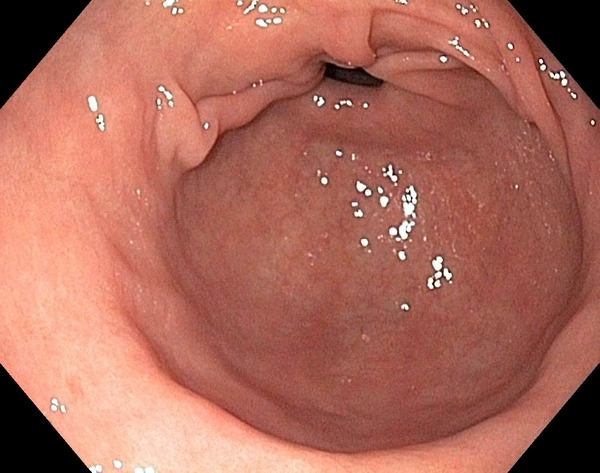

Диагностические признаки антрального гастрита выявляют с помощью эндоскопического оборудования. Слизистую оболочку осматривают через камеру, а патоморфологические изменения определяют методами гистологии.

Диагностические признаки поверхностного антрум-гастрита:

- покраснение, гиперемия слизистой;

- оболочка местами становиться толще;

- углубляются ямки внутри желудка.

При других подвидах болезни заметно существенное изменение строения слизистой органа. В камере видно рубцы, эрозии, участки с перерождённой тканью (разрастание, наличие валиков, уплотнение, полипы, атрофия). Вследствие таких патоморфологических изменений нарушается нормальное соотношение компонентов состава желудочного сока, ухудшается процесс пищеварения и организм недополучает полезные вещества из пищи. Поэтому при запущенном антральном гастрите у человека развивается анемия, возникает истощение.